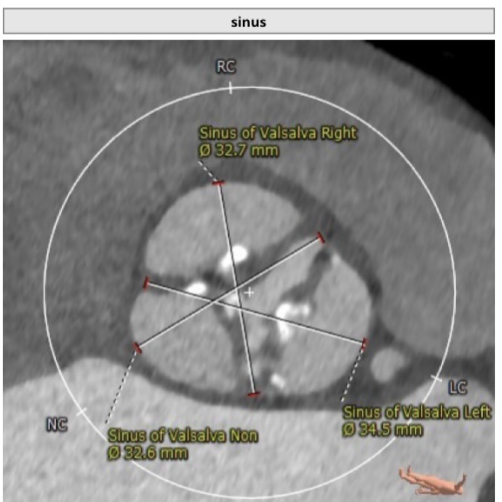

CTA主动脉根部解剖:患者为二叶瓣,重度钙化,瓣环平面可见钙化,可见钙化延伸至左室流出道,右无、左无均可见融合,以右无融合为明显,冠脉高度尚可。升主动脉最宽处为超过 45mm,心脏角度约:49度。

Sinus——32.6*34.5*32.7mm

该病例为:Type1型二叶式主动脉瓣,重度钙化并严重增厚,法式窦结构大,双冠脉开口高度良好,主动脉瓣环夹角可,非横位心,主动脉弓夹角锐利,弓距可,左心室腔增大,推荐右侧股动脉为主入路,左侧辅助入路,建议使用20F戈尔血管鞘,备SNARE;推荐跨瓣角度LAO26°CRA5°左右,推荐使用22mm球囊预扩,角度为LAO22°CRA2°(左冠切线位);推荐预装L26瓣膜,释放角度RAO21°CAU35°(左右重合),释放高度推荐较高位(瓣环下0-2mm)。